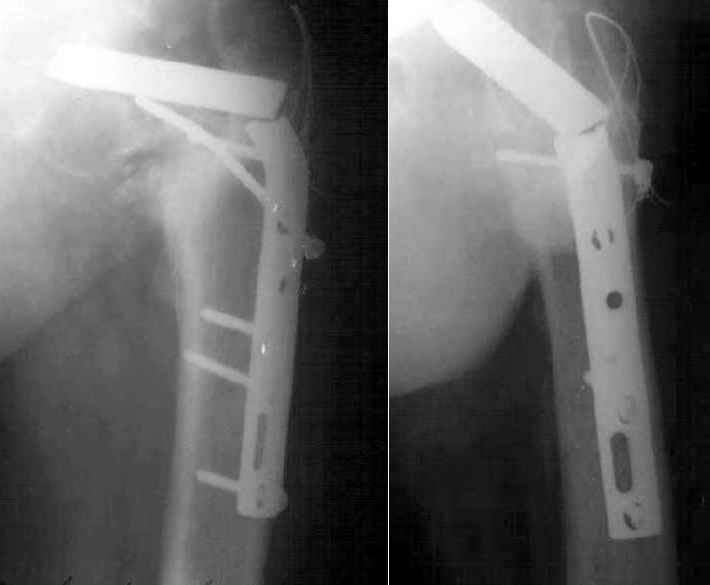

A 35 y.o. male was operated in our facility 1.5 years ago. Walked with cane about 8 months, then with full weight-bearing. Hardware failure was revealed this January. The current situation is presented at the attached image. The head looks not deformed and hip ROM is good. Which way should be preferred?

I also have had reasonable success with valgus producing intertrochanteric osteotomy for femoral neck nonunion especially when the neck shaft angle is down to 90 degrees as in these two cases.